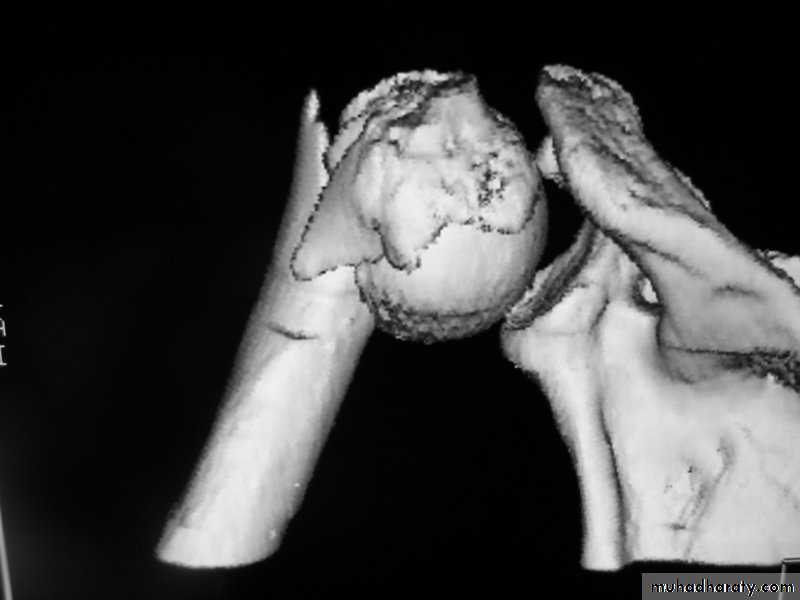

C-T scan

Indications:Segmental bone necrosis.

Depressed fracture in cancellous bone.

Small radiolucent lesion; eg oseoid osteoma.

Bone and soft tissue tumors.

Complex fractures of spine, pelvis, tarsal and carpal bones.

3-D reconstructed images.

Disadvantage: high radiation exposure.

3-D C-T in fracture pelvic ilium

C-T of shoulderMRI